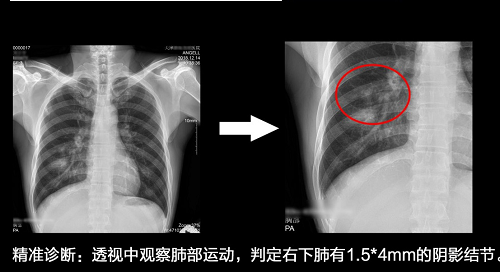

除了功能多,能够拍出清晰片子,能够提供非常精准的图像,对于诊断评估来说尤为重要。目前DR的技术发展已经从传统的静态点片观察发展到动态观察、动静极速切换捕捉病灶。相对于传统的静态观察来说,动态观察能够诊断很多静态点片方式无法诊断的片子,诸如:占位性病变、隐匿性病灶等等、肺结节等识别,往往需要通过CT做进一步的检查来做进一步确认。当前在国内广泛发展的动态DR,则能很好的解决这个问题。动态DR的关键在于,能够突破动态观察病灶与静态高速点片之间的切换问题,要能够以最快的速度实现动静切换,高清点片。其中最关键的就是在最短的时间内实现动态观察病灶和静态捕捉(点片)病灶两者之间的切换,切换越快,越能精准的捕捉关键病灶。